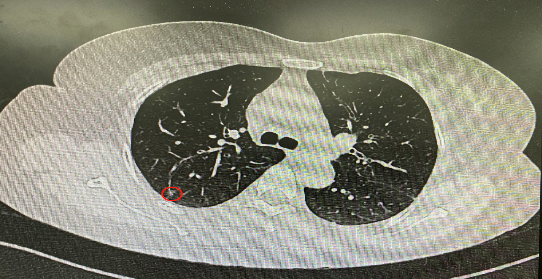

今年54歲的李女士(化名)7月初突然出現(xiàn)右上部腹痛,起初并未在意,以為稍作休息就會好轉(zhuǎn),但疼痛卻并未消退,持續(xù)了一個星期。李女士實(shí)在難以忍受,才在家人陪伴下來到西安國際醫(yī)學(xué)中心醫(yī)院就診。胸外科二病區(qū)崔凱主任接診患者后,詳細(xì)詢問病情并查閱檢查資料,經(jīng)胸部HRCT檢查,結(jié)果提示:右肺上葉后段混合密度結(jié)節(jié)影,考慮原位癌可能,即將患者收入胸腔外科二病區(qū)住院治療。

經(jīng)與患者家屬溝通,崔凱主任決定行外科手術(shù)治療。為達(dá)到精準(zhǔn)切除,術(shù)前需進(jìn)行肺小結(jié)節(jié)切除前定位。由于結(jié)節(jié)位于右肺上葉后段,傳統(tǒng)經(jīng)胸外穿刺術(shù)無法抵達(dá)病灶。崔凱主任與呼吸內(nèi)科一病區(qū)歐陽海峰主任討論后,決定擬行LungPro全肺診療導(dǎo)航下染色定位。即術(shù)前通過Lung Pro導(dǎo)航規(guī)劃染色位置,經(jīng)Lung Pro實(shí)時引導(dǎo)支氣管鏡抵達(dá)既定位置,注入亞甲藍(lán)染色劑標(biāo)記結(jié)節(jié)位置。

使用術(shù)前規(guī)劃系統(tǒng)重建全肺3D模型,并于外科醫(yī)生討論染色位置,最終確定標(biāo)記染色點(diǎn)—右肺上葉后段b亞段(RB2b)。術(shù)中使用P290(4.9mm外徑)標(biāo)準(zhǔn)支氣管鏡,根據(jù)導(dǎo)航術(shù)前規(guī)劃路徑,Lung Pro實(shí)時導(dǎo)航下,GS鞘管進(jìn)入RB2b遠(yuǎn)端官腔外病灶并注射亞甲藍(lán)染色劑。

一切準(zhǔn)備就緒,7月15日,崔凱主任團(tuán)隊(duì)聯(lián)合歐陽海峰主任團(tuán)隊(duì)為患者行單孔胸腔鏡下右肺上葉后段切除術(shù),手術(shù)用時128分鐘順利完成。進(jìn)入胸腔后,亞甲藍(lán)染色部位明顯,患者發(fā)生癌變的右肺上葉后段被成功切除。術(shù)后標(biāo)本根據(jù)染色部位迅速找到結(jié)節(jié),剖開位置兼染色位置和病灶完全符合,行術(shù)中冰凍后快速送病理檢查。經(jīng)術(shù)后病理檢查,明確診斷為(右肺上葉)原位腺癌。